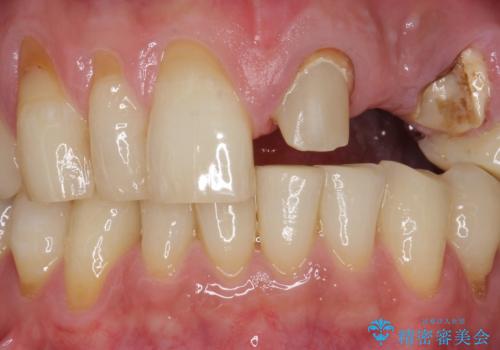

- ブリッジの支台歯であった左上の犬歯が折れたことを主訴に来院された患者様です。

犬歯は歯ぐきの奥深くまで割れており保存不可能な状態でしたが、どうしても抜きたくないとのことでした。

歯を牽引し健全歯質を歯肉縁上まで引き上げ、歯の保存を試みることにしました。